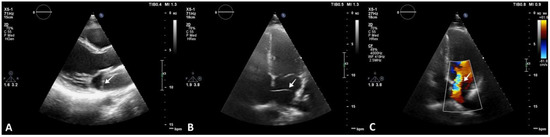

In order to better visualize the identified structure within the LA, a transesophageal echocardiography was performed. The membrane stretched out from the interatrial septum right beneath the foramen ovale to the lateral atrial wall above the LAA (Figure 3).

Figure 3.

Transesophageal echocardiography revealing CTS. (A) and (B) show 2D and 3D reconstructions visualizing the membrane and its fenestrations (arrow).

Multiple membrane fenestrations ensured the connection between the proximal and distal LA chambers. Color Doppler interrogation of the interatrial septum revealed PFO with minimal spontaneous left-to-right shunt (Figure 4).

Figure 4.

Transesophageal echocardiography revealing CTS. (A) Image showing openings in the CTS membrane (arrow). (B) PFO with minimal spontaneous left-to-right shunt (arrow).